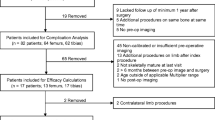

Prior to starting this investigation, we obtained Institutional Review Board (IRB) approval at our medical center. The IRB waived the requirement for informed consent. We reviewed the medical records and radiographs of 16 patients who were treated with PETS for a predicted LLD >2.5 cm at skeletal maturity. Sixteen patients (12 boys and 4 girls) were treated for LLD with PETS in the distal femur and proximal tibia in 15 patients and distal femur in only 1 patient. The average chronologic age at the time of surgery was 14 years (range 11.7−16.1 years) and the average follow-up was 2 years (range 0.7−5.2 years). The etiology of the LLD included 7 congenital, 6 acquired secondary to Legg−Calvé−Perthes disease, fracture causing growth arrest, slipped capital femoral epiphysis, and 3 unknown.

The PETS technique was successful in decreasing the LLD in 15 of the 16 patients (94 %) patients (Fig. 4). One boy with a preoperative chronologic age of 16 years (bone age 14) showed no improvement in LLD. The average preoperative LLD was 3.1 cm (range 1.3−6.0 cm). The average LLD at maturity was 1.7 cm (range 0.4−3.1 cm) for an average correction of 1.4 cm (range 0.0−4.0 cm; p < 0.001) as shown in Table 1.